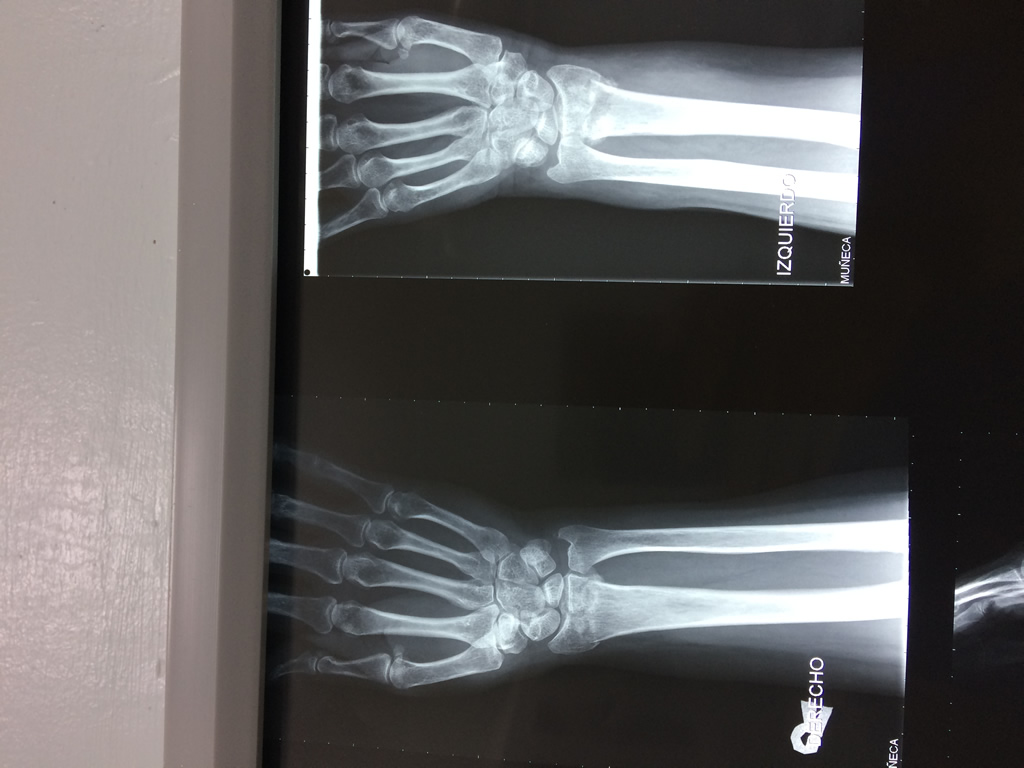

Húmero - Cirugías de Muñecas y Manos

Los procedimientos más comunes en cirugía de la mano son aquellos destinados a reparar traumatismos, incluyendo lesiones de tendones, nervios, vasos sanguíneos, y articulaciones; huesos fracturados; y quemaduras, cortes, y otros daños de la piel.